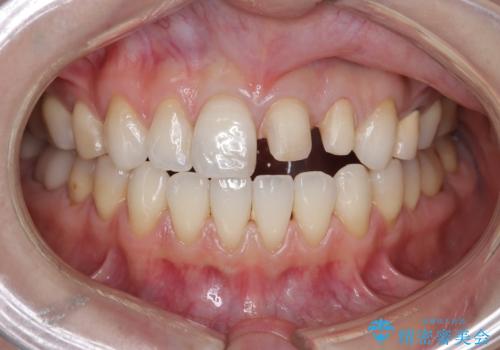

- 「前歯の色が気になる」を主訴に来院された患者さんです。以前他院にて、前歯2本をCR(プラスチック)で治療されていたところが劣化し変色していました。歯の長さも左右で異なっている状態でした。大部分がCR(プラスチック)修復されていたので、オールセラミッククラウンで治療を行いました。

古いCR(プラスチック)とその下の虫歯を除去した後に新しい土台を立てています。適合が良い被せ物を作るために拡大鏡を使用しながら歯を削り、変形のほとんどないシリコンという材料で型取りを行っています。